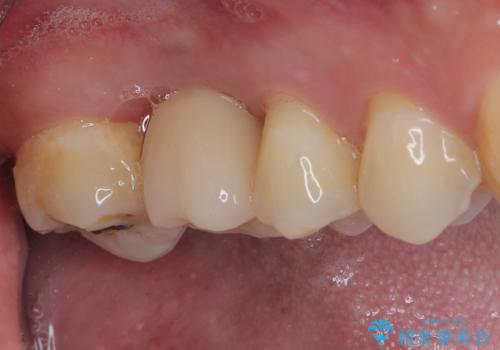

インプラントが生着するのを待っている間に反対側の根管治療を行い、左右同時に補綴治療を行いました。

補綴治療後3ヶ月での経過は良好で、引き続き経過観察を行っていきます。